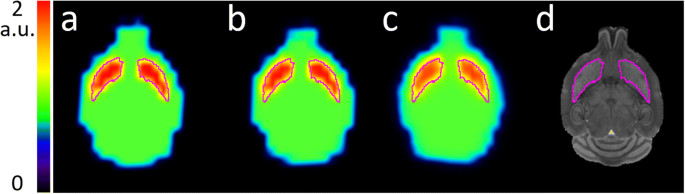

The measured average speed of the mouse in the naïve condition was 1.55 cm/s, while for the memantine challenge condition, it was 4.57 cm/s. Figure 4 shows the numerical mouse brain phantom images after blurring by the residual motion kernels in all conditions.

Fig. 4

figure 4

Transverse slices of the numerical mouse brain phantom with activity in the striatum, delineated in purple. Numerical phantom (a) reference (unblurred), (b) naïve mouse motion blurred, (c) memantine challenge motion blurred, and (d) MRI for anatomical reference

The average striatum activity in the reference image is 1.65. After residual motion blurring, the average striatum activity reduces to 1.64 and 1.52 for the naïve and memantine challenge conditions respectively, i.e., a difference of − 0.61% and − 7.9% with respect to the reference. The difference between naïve and challenge conditions is 7.3%.